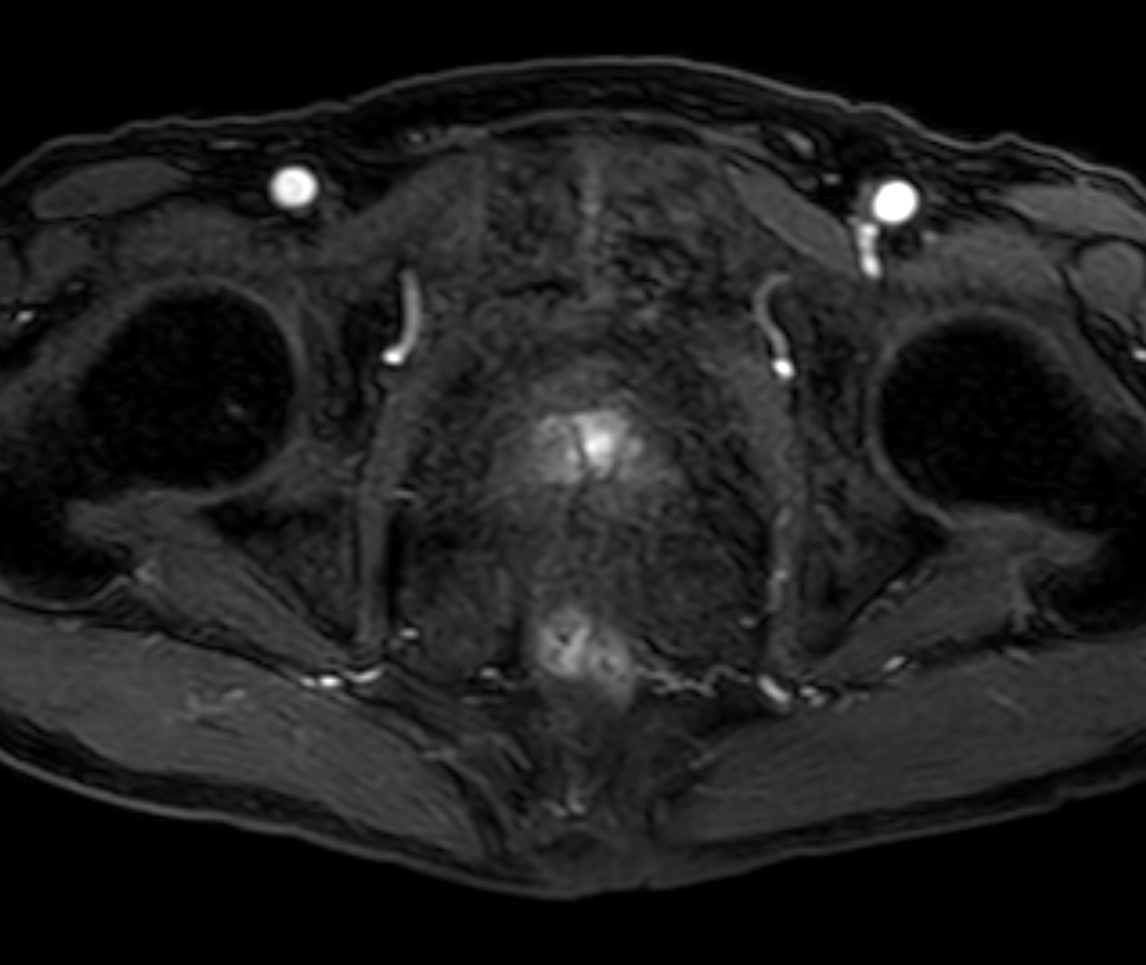

Axial T2w TSE